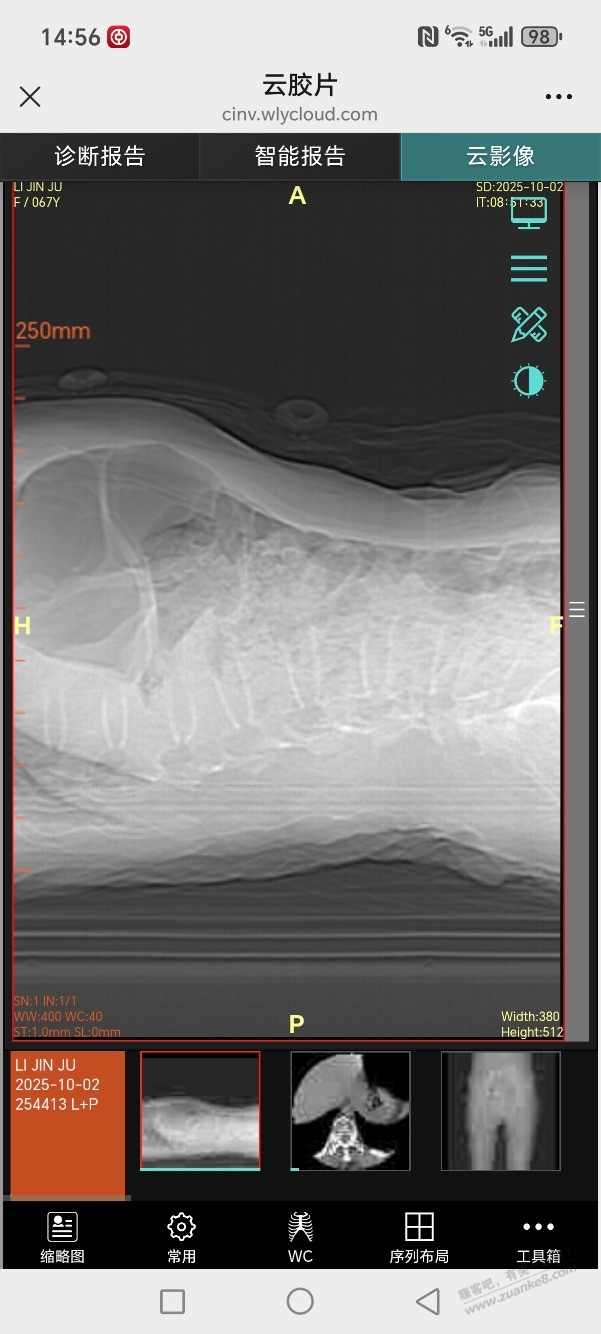

[大家谈谈] 腰椎L1压缩性骨折做骨水泥手术得多少钱

镇上医生说保守治疗,市里医生让做微创骨水泥